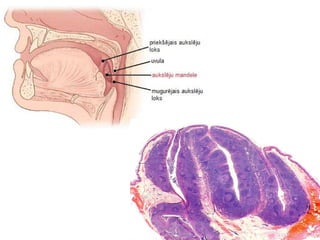

Aukslēju mandeles (2)

● ovālas formas limfoīdie audi, kas

novietotas starp priekšējiem un

mugurējiem aukslēju lokiem

● tām izšķir 2 virsmas (mediālo,

laterālo) un 2 polus (augšējo,

apakšējo)

● ietvertas saistaudu kapsulās

● apasiņo 5 artērijas, venozā attece

uz v.facialis

● limfas attece uz dziļajiem kakla

Aukslēju mandeles (2) ●ovālas formas limfoīdie audi, kas novietotas starp priekšējiem un mugurējiem aukslēju lokiem ● tām izšķir 2 virsmas (mediālo, laterālo) un 2 polus (augšējo, apakšējo) ● ietvertas saistaudu kapsulās ● apasiņo 5 artērijas, venozā attece uz v.facialis ● limfas attece uz dziļajiem kakla limfmezgliem ● inervācija - n.glossopharyngeus, šķiedras no ganglion sphenopalatina